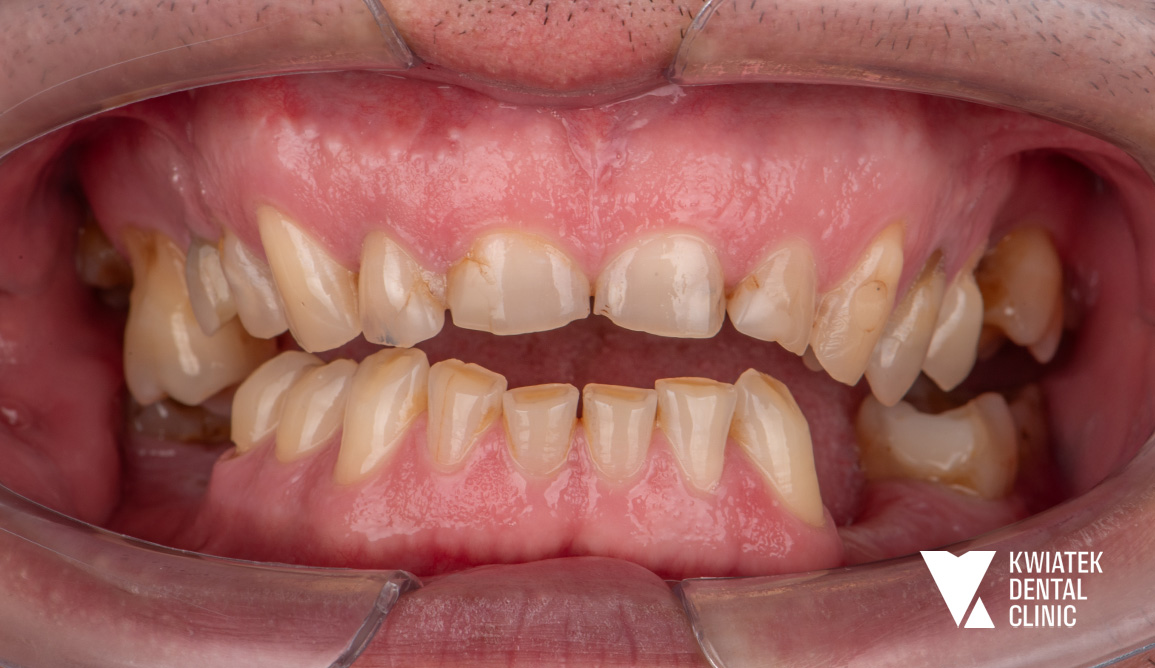

Pełna rekonstrukcja zwarcia i estetyki - historia wymagającej metamorfozy

Pacjent zgłosił się do kliniki z zaawansowanymi problemami stomatologicznymi: licznymi ubytkami próchnicowymi, brakami zębowymi, starciem zębów oraz zaburzeniami zwarcia. Leczenie obejmowało kompleksową diagnostykę, leczenie zachowawcze i endodontyczne, zabiegi chirurgiczne, implantację oraz wieloetapową odbudowę protetyczną. Efektem terapii jest perfekcyjnie zbalansowany zgryz, najwyższy komfort funkcjonowania oraz naturalnie piękny uśmiech, który podkreśla indywidualny charakter pacjenta i pozwala mu w pełni cieszyć się nim każdego dnia.